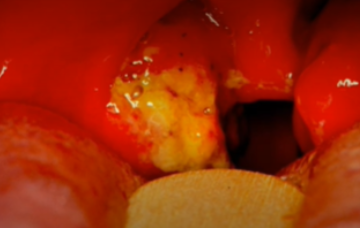

Candida Albicans

One of the 10 Common Abnormalities of the Mouth

Fungal infection caused by an overgrowth of Candida albicans in the mouth

Presents as creamy white, curd-like patches on the tongue, inner cheeks, gums, or throat, which may be painful or cause a burning sensation

patches can be scraped off, leaving a red or bleeding surface